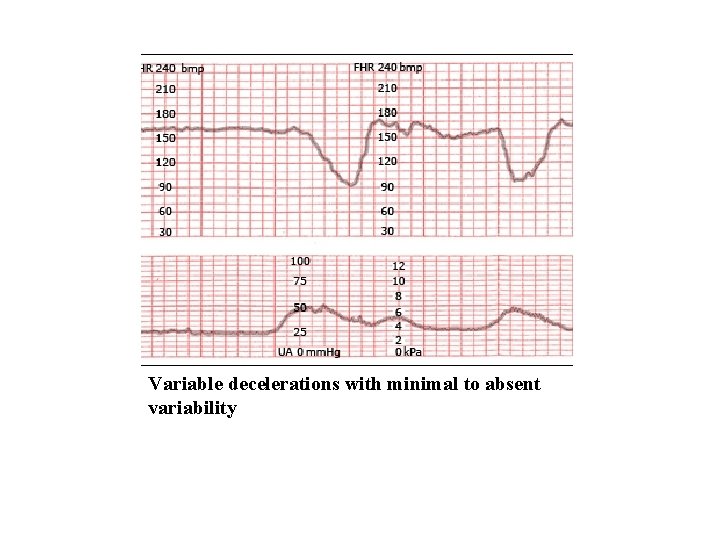

variable decelerations with absent to minimal variability

Variable decelerations with minimal to absent variability